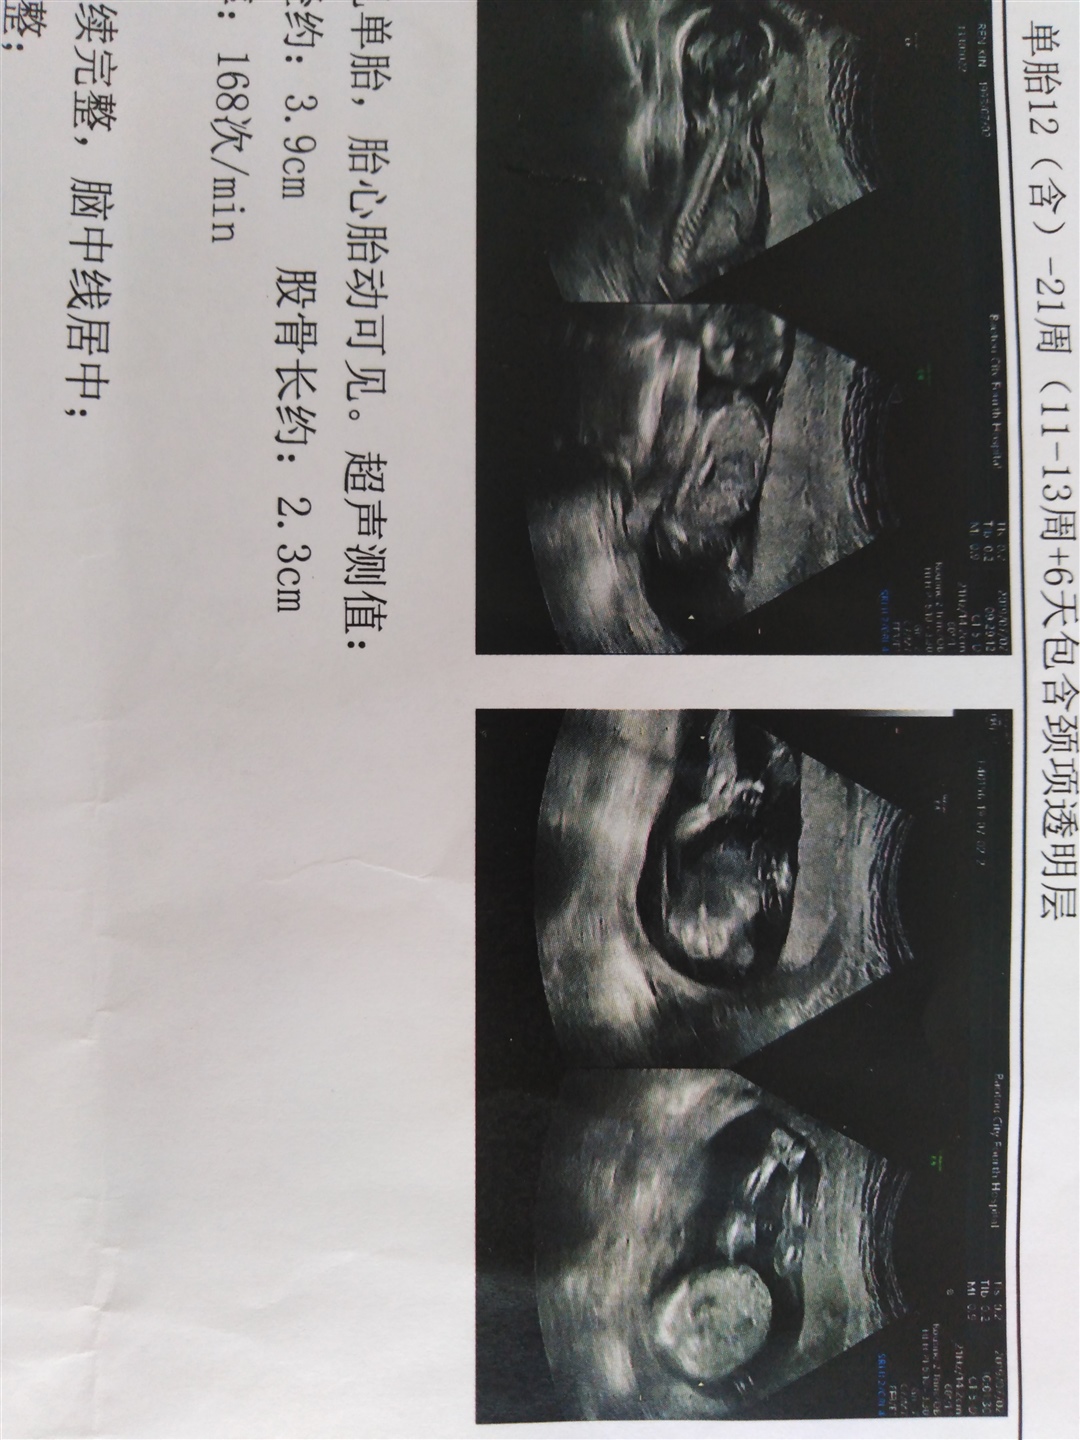

孕17周+6天

男